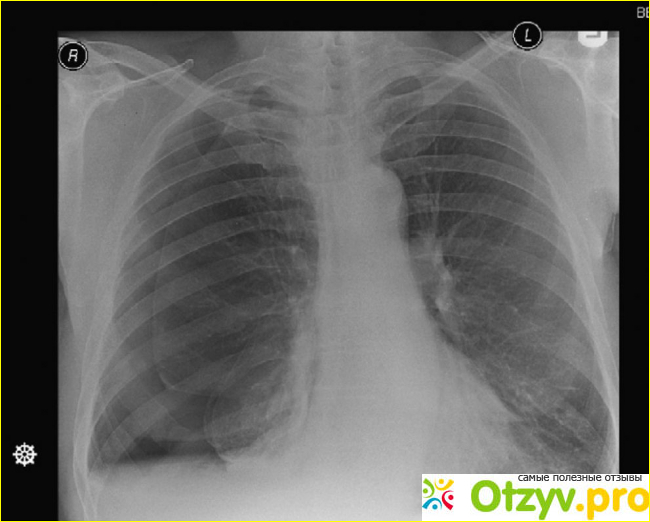

На тот момент сильно повысилась температура и давления, меня бросило в озноб. Не стали терять время и меня повезли в районную больницу, именно там я и познакомился с Чемяновом Георгием Станиславовичем. В своем отзыве я хочу рассказать о том, как со мной вел себя данный лже-специалист. Позже я пробил про него информацию, и отзывы почитал дополнительно на местном сайте, где многие его пациенты тоже остались недовольными качеством его работы. Он сразу принялся меня правда осматривать, после моего ответа на вопрос по поводу сигарет, он начал на меня сражу же косо смотреть и перешел на другой не очень приятный мне уровень общения. Отправил в грубой форме проходить рентген, на котором выявилось что в плевральной полости левого легкого у меня достаточное количество жидкости и воздуха, которые в скором порядке нужно было выкачивать. Называется данная болезнь - спонтанный гидропневматоракс, вот и произошла она довольно случайно и не в самый подходящий момент. Хорошо, что меня навещали за 2 недели моего нахождения в данной больнице, мои лучшие друзья, близкие люди и напарники с работы. За это время я съел столько апельсинов, бананов и яблок, сколько за год не ел. И благодаря тому, что я просто хотел перебороть данную болезнь, мне в конечном итоге удалось встать на ноги.